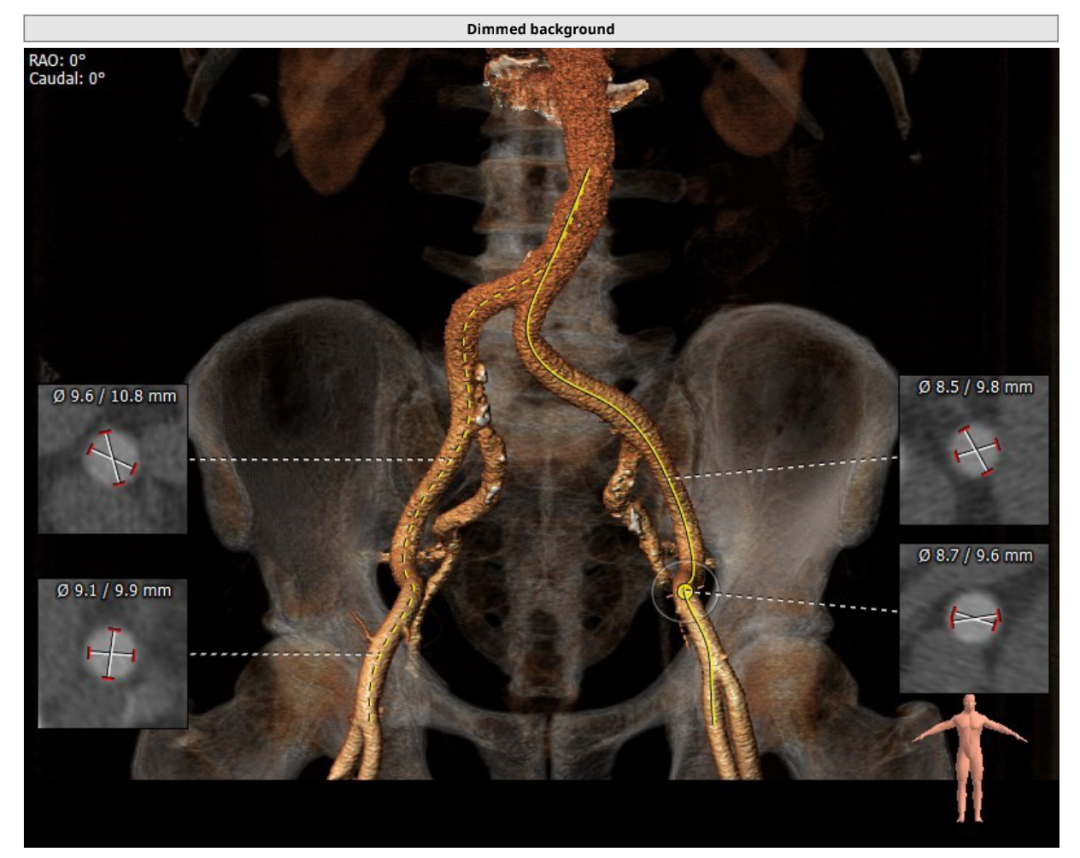

入路情况